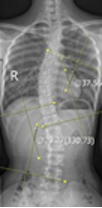

通过自测,如果认为身体存在脊柱侧弯的可能性,就一定要去医院检查。根据脊柱侧弯的角度(Cobb角)大小不同,处理的方法也不同。【Cobb角的测量方法:先确定侧弯的端椎,上、下端椎是指侧弯中向脊柱侧弯凹侧倾斜度最大椎体。在上端椎的椎体上缘画一条横线,同样,在下端椎的椎体下缘画一条横线。对此两横线各做一垂直线,然后测量两条直线的夹角。】